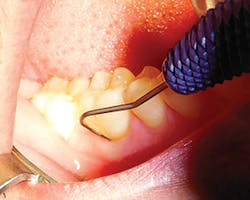

Secondly, gently retract the patient's lip or cheek to gain access, place the periodontal probe on the outside of the tissue, and measure from the gingival margin to the mucogingival junction, and record (see Figure 3).